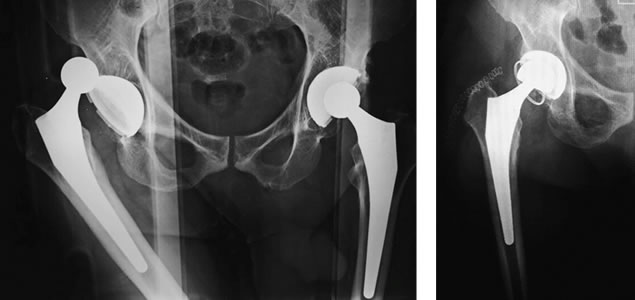

La incidencia de luxación en un reemplazo total de cadera varia del 1 al 4 %, consecuentemente, la inestabilidad protésica es la causa más frecuente de indicación de una cirugía de revisión. La mayoría de las luxaciones ocurren dentro de los primeros tres meses de la cirugía, por lo tanto, respetar los cuidados según protocolo postoperatorio son de vital importancia. Existen múltiples causas de inestabilidad y en muchos casos, incluyen varios factores: por lo tanto, el tratamiento es específico para cada paciente.